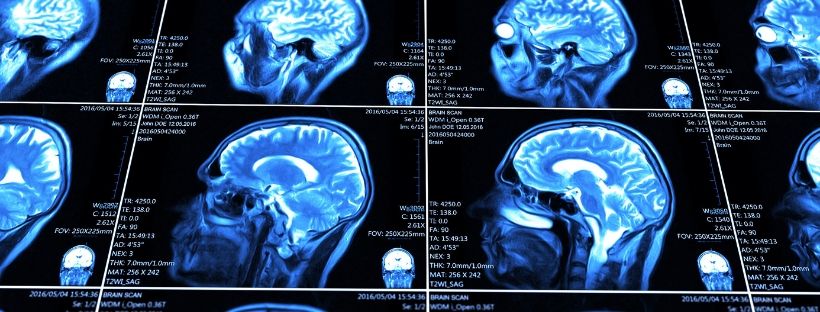

Risonanza Magnetica

La Risonanza Magnetica (RM) è una metodica che ha fatto la sua comparsa nel campo della diagnostica..